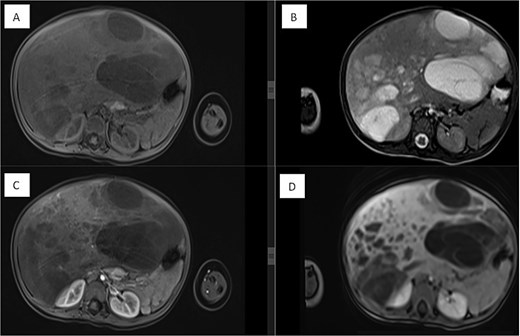

Several months later, she developed progressive abdominal distension and recurrent vomiting, prompting further evaluation. A CT scan of the abdomen revealed a large heterogeneous hepatic mass primarily occupying the right lobe, measuring 12.6 × 8.8 × 14 cm, with multicystic areas and soft tissue enhancement. MRI also demonstrated a large right hepatic lobe mass with mass effect and heterogeneous enhancement (Figs 1 and 2). Mild upper abdominal lymphadenopathy was noted (largest node 8 × 10 mm), along with a right-sided inguinal hernia. Differential diagnoses included HMH, with hepatoblastoma and undifferentiated sarcoma considered less likely. A chest CT showed mild pericardial effusion and an inflammatory appearance.

Dynamic MRI of the abdomen demonstrating a large, partially cystic, and solid lesion arising from the right hepatic lobe. (A) Axial T1 and (B) axial T2 images show the lesion’s mixed composition and internal structure. (C) Arterial and (D) portovenous phase post-contrast images reveal heterogeneous enhancement of the solid and septal components.